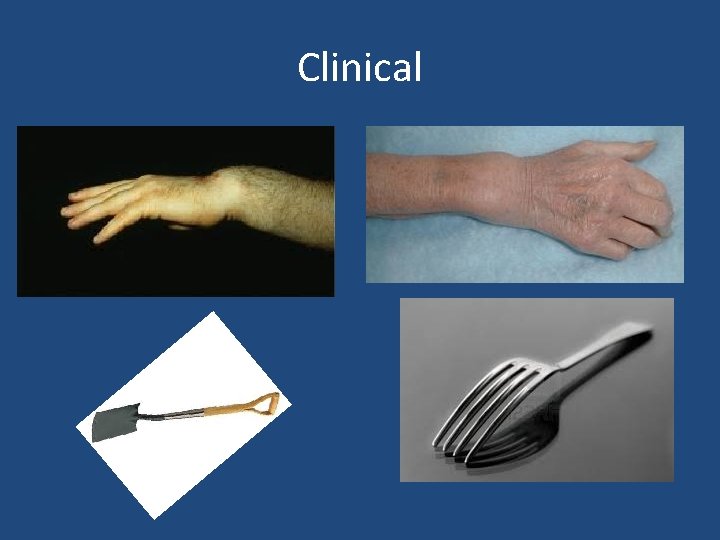

Clinical

X-rays Colles’ Smith’s